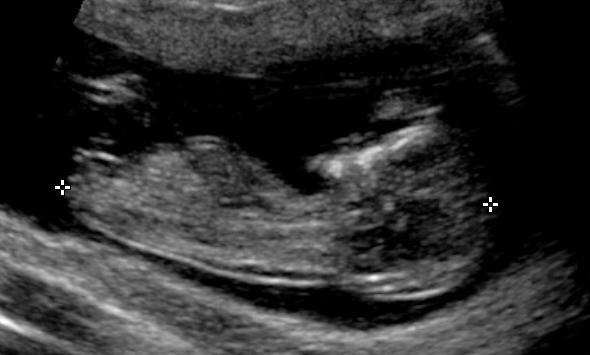

This is our first baby and I am dying to know the gender. Please see attached a few photos from our 12 week scan. What do you think - boy or girl????

Girl by NUB and skull 💝